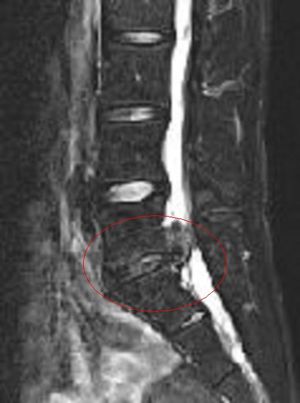

표시된 부분이 압박된 신경근]]3. 2. 감별 진단

'''빨간 원 안은 '압박된 신경근' 및 '수분 함량이 부족하고 염증을 일으켜 위로 크게 돌출된 추간판'''']]

'''위 이미지의 고농도 버전'''